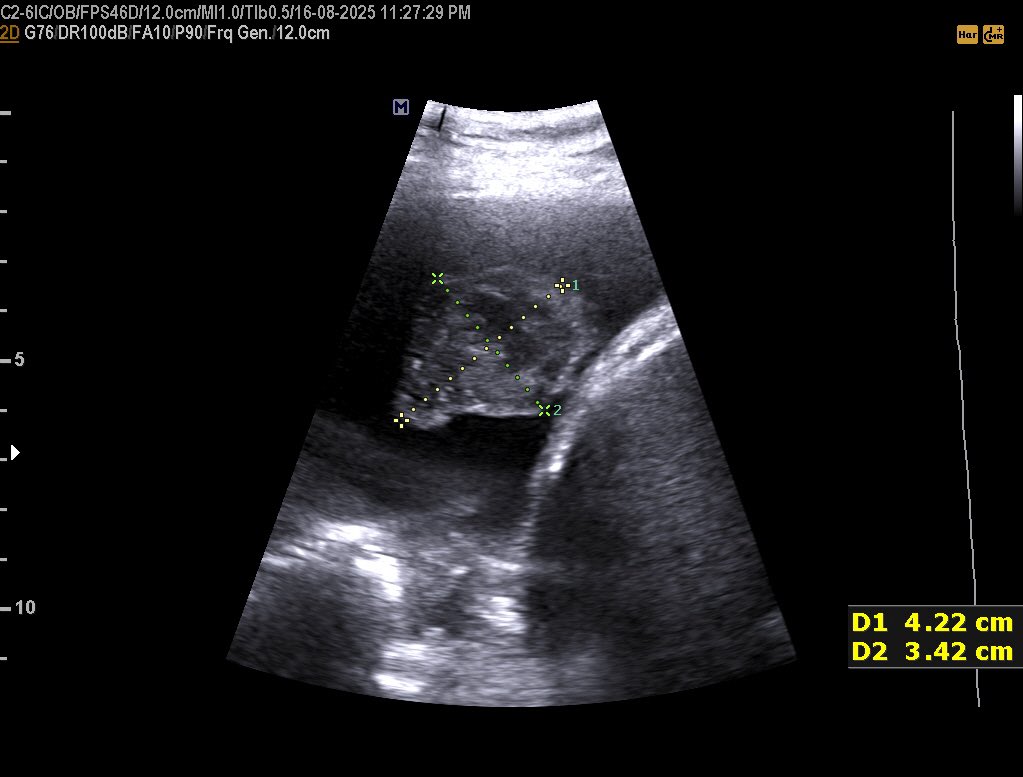

𝗖𝗘𝗥𝗩𝗜𝗖𝗔𝗟 𝗟𝗘𝗡𝗚𝗧𝗛 𝗜𝗡 𝗨𝗟𝗧𝗥𝗔𝗦𝗢𝗨𝗡𝗗 Normal Cervical Length : ≥25 mm Risk starts : <25 mm Serious risk : <15 mm #EchoTech

𝗖𝗘𝗥𝗩𝗜𝗖𝗔𝗟 𝗟𝗘𝗡𝗚𝗧𝗛 𝗜𝗡 𝗨𝗟𝗧𝗥𝗔𝗦𝗢𝗨𝗡𝗗 Normal Cervical Length : ≥25 mm Risk starts : <25 mm Serious risk : <15 mm #EchoTech

𝗖𝗘𝗥𝗩𝗜𝗖𝗔𝗟 𝗟𝗘𝗡𝗚𝗧𝗛 𝗜𝗡 𝗨𝗟𝗧𝗥𝗔𝗦𝗢𝗨𝗡𝗗 Normal Cervical Length : ≥25 mm Risk starts : <25 mm Serious risk : <15 mm #EchoTech